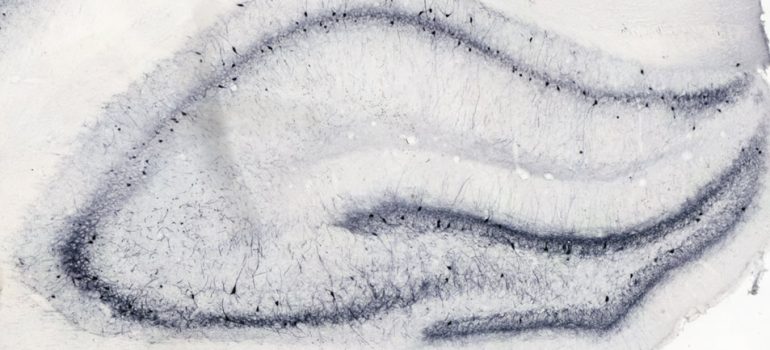

We routinely collect post-mortem samples (e.g. brain and blood) for ex vivo analysis to assess the effect of compounds on relevant biomarkers to understand mechanisms underlying efficacy in the model.